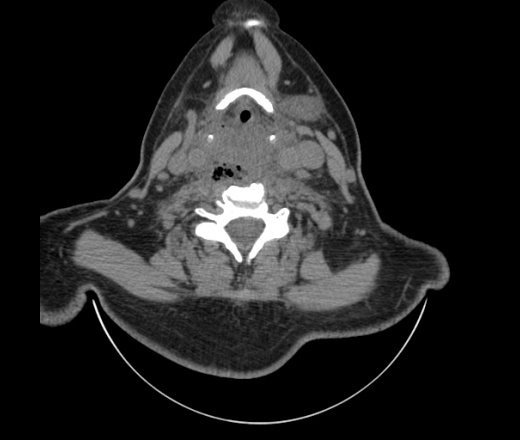

Женщина поступила в х/о спустя 4 дня после того как при употреблении карася подавилась костью.

Наличие газа в средостении на протяжении тел С2-С6 (медиастинальна эмфизема); рыбная кость на уровне тела С6.

При всем уважении, но говорить о медиастинальной эмфиземе, оценивая мягкие ткани шеи, как-то слишком резко. На мой взгляд, это ретрофарингеальное пространство.

Эвакуировали почти 100мл гноя. Но кость не смогли найти. Думаю что она даст дальнейшее ослоднение. Эндоскопически за черпалонадгортаной звязкой не смогли зайти в пищевод, все мягкие ткани отечные, просвет пищевода сдавлен. По всей видимости параэзофагеальная клетчака тоже задействована. Эмпиема, если ее можно так назвать, незнаю как правильно дошла до уровня яремной вырезки. Чем закончиться напишу. Ждем медиастинита.

Флегмона заглоточного пространства шеи, только операция, флегмоны вскрывают. Риск медиастинита.

Согласен с Вами; конечно, наличие газа в клетчатке ретрофарингеального пространства (затмение с опечаткой..). К сожалению, процесс "продвигается" к медиастиниту. Но почему никто, не отмечает наличие рыб. кости; или это для Всех очевидно?

Так вы уже отметили. Хотя ориентировал бы не скелетотопически, а на перстнечерпаловидный сустав.

Кость то мы сразу выявили, размеры где то 17*2мм, но ее так и не получается найти в этой каше